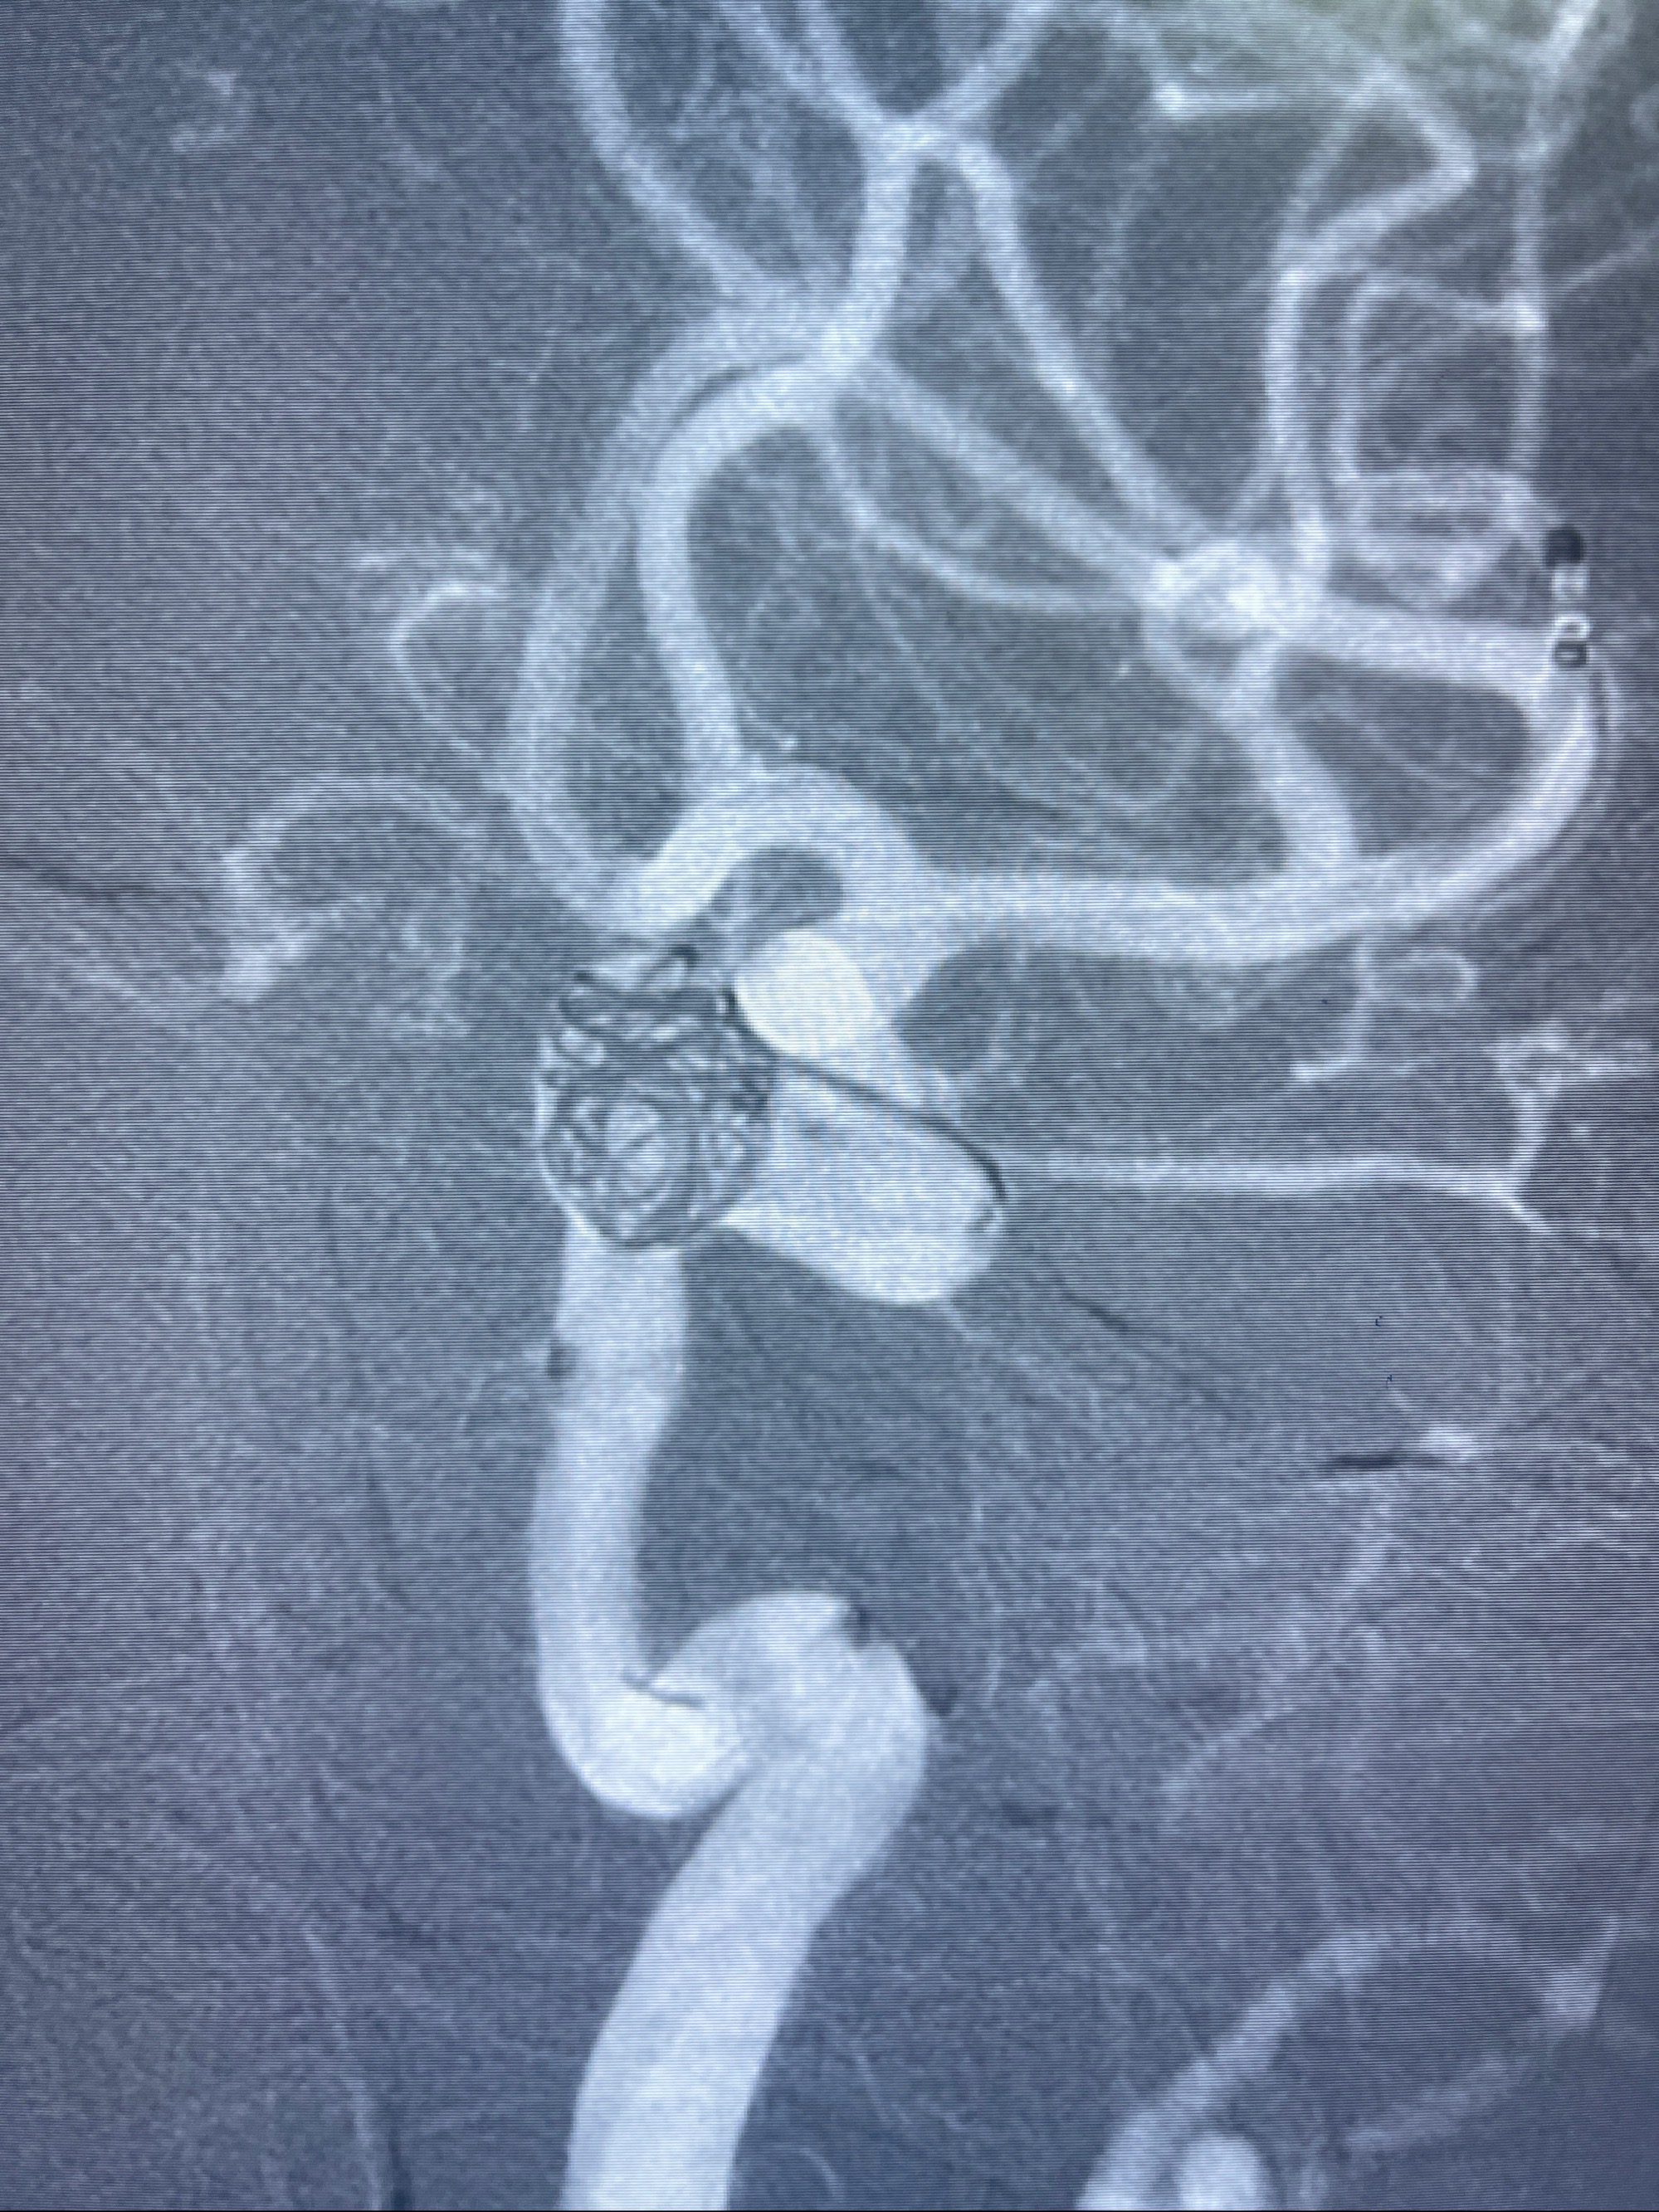

2023-08-30DSA:左侧颈内动脉眼动脉动脉瘤,约3*9.2*7.3mm大小

- Tubridge 4.0-20mm密网支架

- 加奇微弹簧圈:7*30/6*20/5*20/2*8

术后3D显示支架贴壁佳